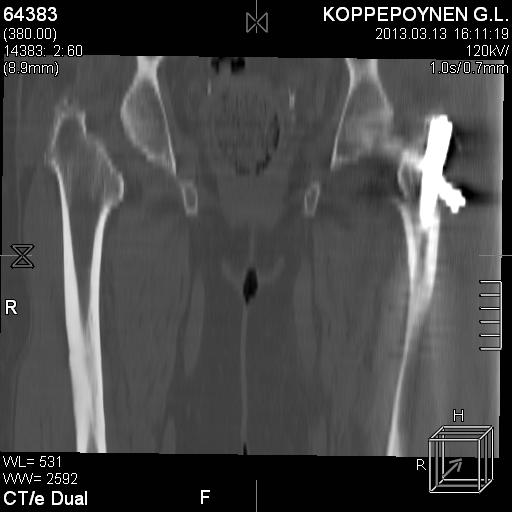

[Ortho] Чрезподвертельный перелом бедра. Остеосинтез стержнем. Перелом металлофиксатора. Дальнейшая тактика?

Делали КТ после операции.